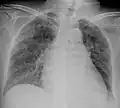

A case of miliary tuberculosis in an 82-year-old woman:

X-ray, 22 days after onset, showing extensive bilateral reticulo-nodular infiltrates -